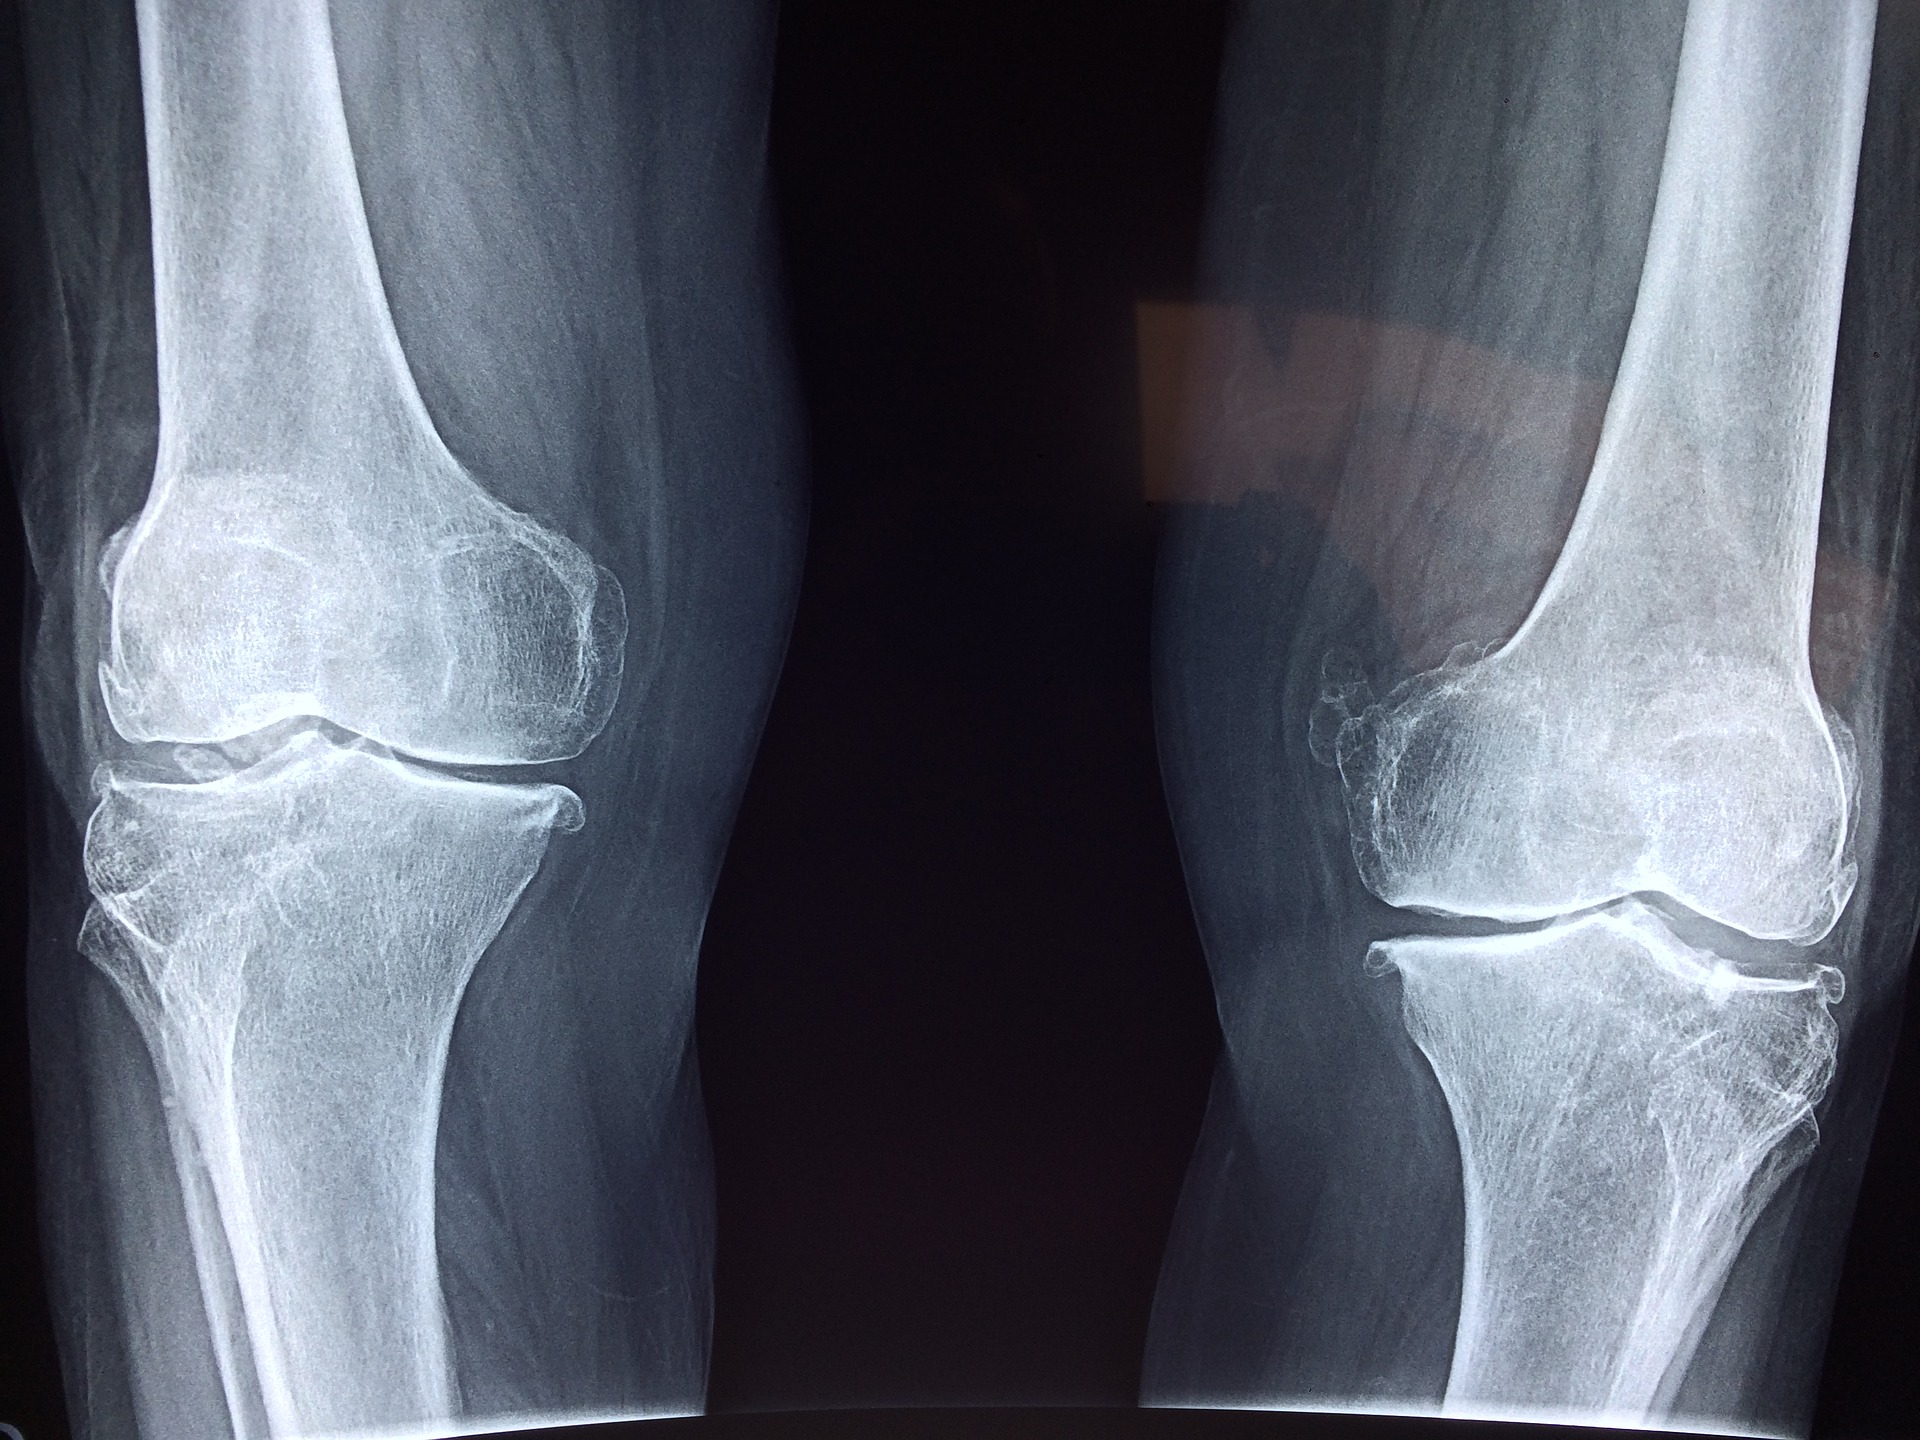

Obecnie bardzo wiele spotyka nas różnych wypadków. Bardzo intensywny tryb życia czy aktywne uprawianie sportu …